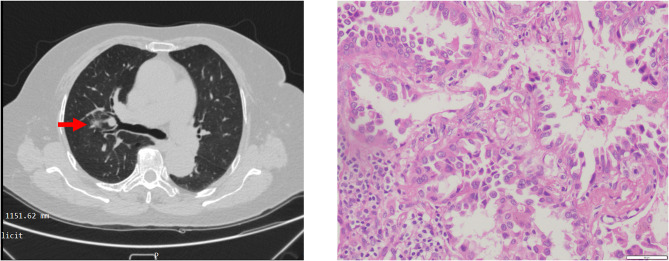

Methods: From October 2020 to June 2023, 14 patients, with unstable angina and resectable lung cancer received PLHS. All procedures were performed in a hybrid operating room. Drug-eluting stents (DES) were implanted during PCI. Lobectomy was carried out within one hour after PCI.

Results: Procedural success was 100%. All the patients subjected to PLHS were alive after 12 months of follow-up; 2 patients (14.29%) died due to distant metastasis within 12-24 months post-PLHS. There were no intraoperative complications, or 30-day- and 3-month-mortality. Except for one patient who suffered pneumothorax, no other postoperative complications, including severe bleeding, or in-stent restenosis, occurred in the 31.7 ± 10.9 months follow-up.

Conclusions: PLHS is a feasible and potentially safe option for patients with both lung cancer and severe CHD.